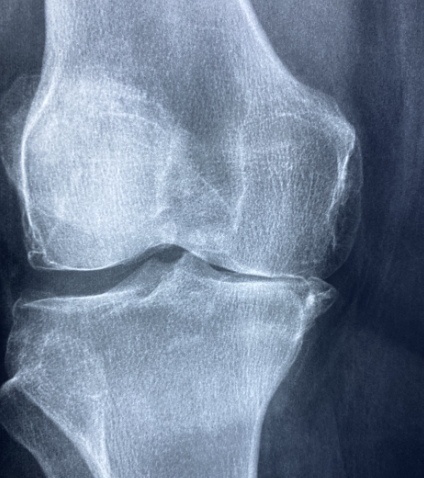

글루코사민은 연골을 구성하는 물질의 하나로, 연골과 관절액의 생성과 유지에 도움을 줍니다. 글루코사민 보충제는 연골이 마모되는 것을 늦추고 관절의 유연성과 움직임을 개선하는 데 효과적입니다. 특히 무릎 관절염이나 연골 손상으로 인한 통증 완화에 자주 권장됩니다.

콘드로이틴은 연골 내 수분을 유지시켜 연골이 탄력과 충격 흡수 기능을 유지하도록 돕는 성분입니다. 글루코사민과 함께 복용하면 시너지 효과가 있으며, 관절의 염증과 연골 분해를 억제하는 데 긍정적인 역할을 합니다.